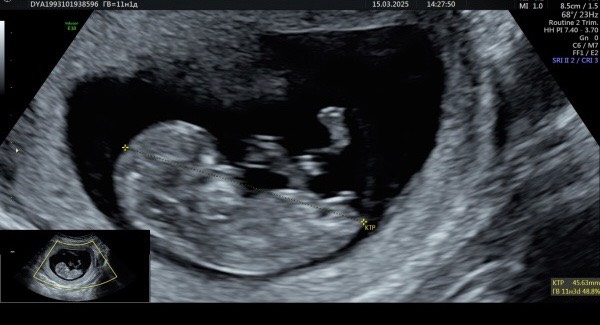

Была сегодня на узи, тк дочка пнула в живот🤦♀️все хорошо

Уже там не криветочка,а целый человек. После узи дочка подошла к врачу и спросила-«кто там у меня будет братик или сестричка?» это было так мило…☺️